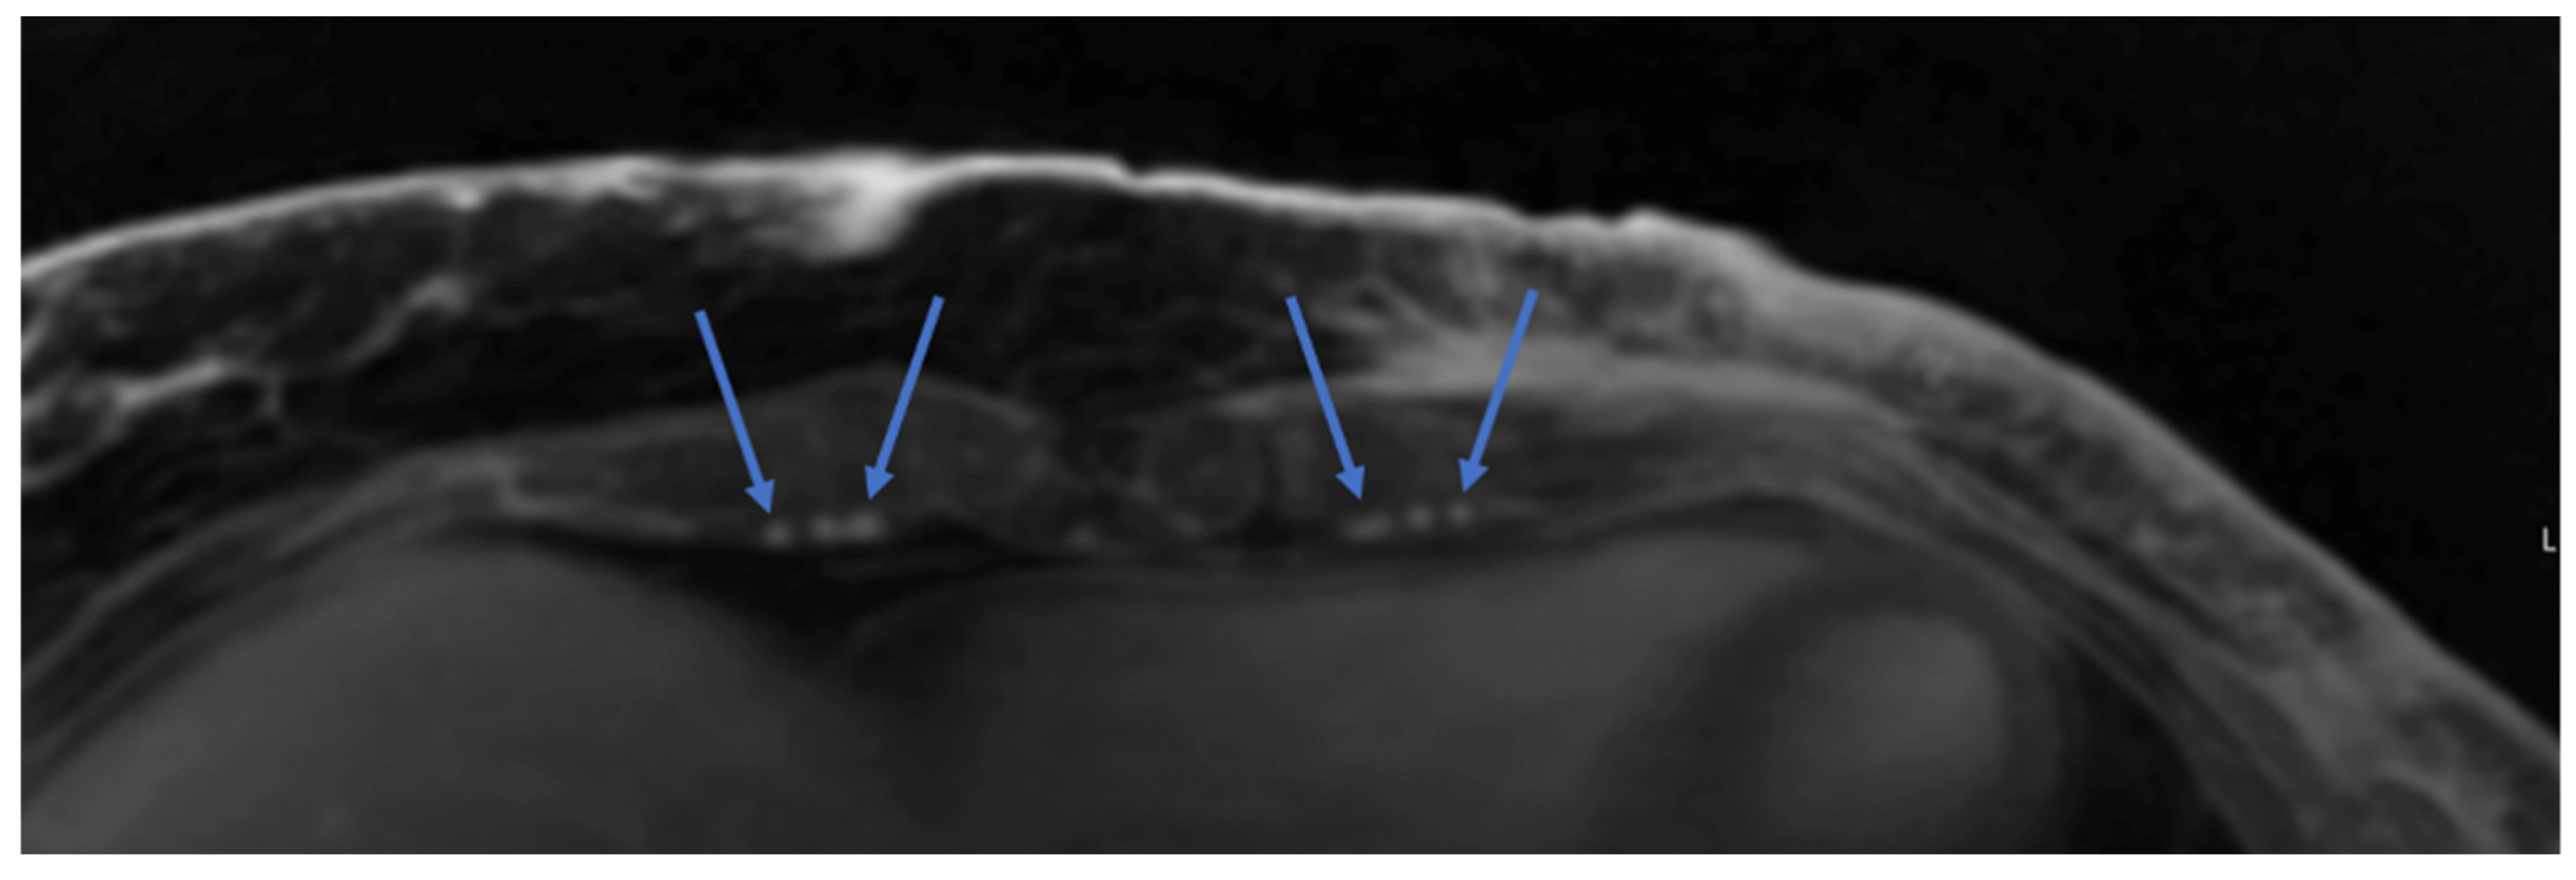

5. Dye-Based and Indocyanine Green (ICG) Angiography